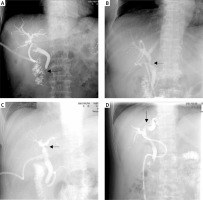

In addition, this study still has some limitations. Because the judgment of POBS is mainly based on the imaging examination in the follow-up period, some patients will be misjudged and missed. In clinical practice, it was also found that some patients only had biliary stricture on imaging (Photo 2), but the clinical symptoms, signs or endoscopy did not show corresponding characteristic changes. Conversely, some imaging examinations could not display the abnormalities of biliary stricture [32]. Thus, invasive surgery such as endoscopic techniques can assist surgeons in the diagnosis and treatment of biliary stricture under direct vision. Various endoscopic techniques can have different effects on the prognosis of patients with benign and malignant biliary stricture, and their surgical success rate, bile duct restenosis and functional recovery vary [1, 33]. However, as in non-invasive diagnostic methods, “stenosis” in the imaging report can indicate the possible pathophysiological changes of the surgical patient, facilitate the formulation of a diagnosis and treatment plan that is beneficial to the patient, and as a transcendental examination method, facilitate the early treatment of biliary complications, actively intervene, and reduce organ function damage.